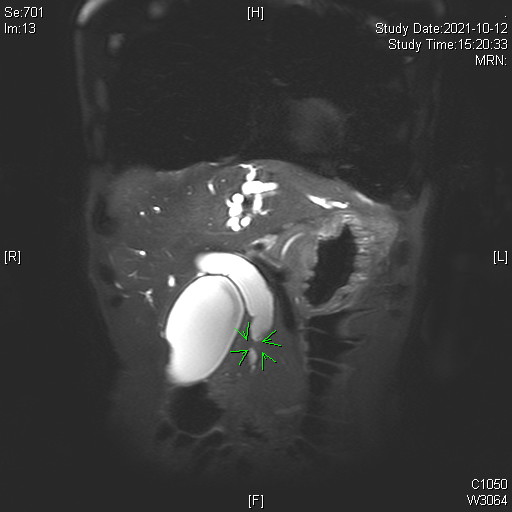

1. Multiphase CT and MRI

- High-resolution contrast-enhanced CT and MRI scans are first-line tools for evaluating biliary masses, ductal obstruction, vascular involvement, and metastatic spread.

- MRI with MRCP (Magnetic Resonance Cholangiopancreatography) is particularly useful for visualizing the biliary tree non-invasively and assessing the level and extent of bile duct strictures or masses.